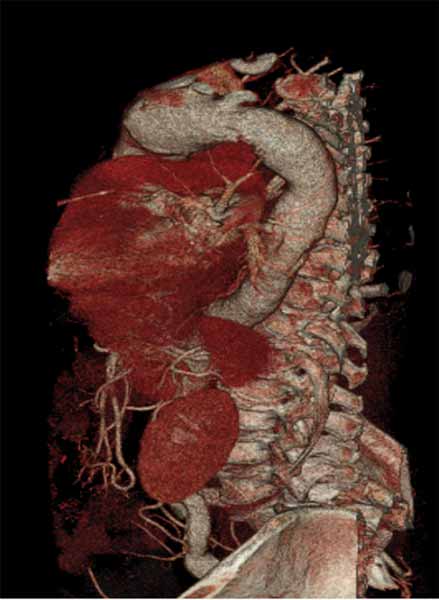

| FIGURE 1-3: 2D and 3D preoperative CT Images of a 78 year old man with aortic insufficiency, and ascending, arch and descending aortic aneurysm with mural thrombus. | |

Appropriate patients for this procedure have extensive thoracic aortic disease and a suitable landing zone for a stent graft in the descending aorta. Many of these patients are candidates for a 2-stage procedure, and selection is based on expected outcomes and the estimated interval rupture risk if patients were to be treated in a staged fashion. (see Figs. 1-3)